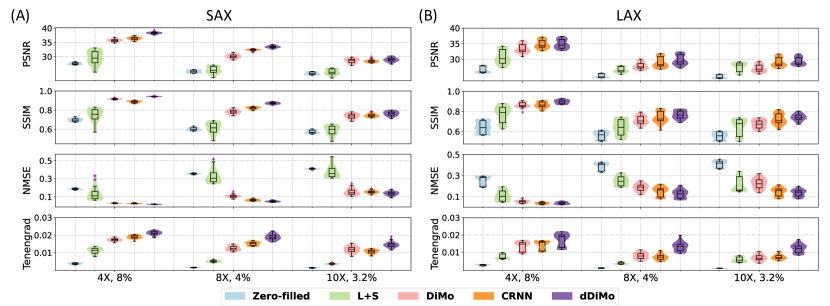

Quantitative results for SAX and LAX views of cine reconstruction are summarized in Table 1. Metrics such as PSNR, SSIM, NMSE, and Tenengrad confirm that dDiMo consistently outperforms baseline methods in acceleration factors (4, 8, and 10) and cardiac views. Even at higher acceleration rates, where reconstruction becomes more challenging, dDiMo demonstrates superior performance across all metrics, highlighting its robustness. Violin plots in Figure 6 provide a visual comparison of the distributions of PSNR, SSIM, NMSE, and Tenengrad metrics for different acceleration settings. dDiMo achieves the highest median values for PSNR, SSIM, and Tenengrad and the lowest NMSE, with minimal variability and fewer outliers. This demonstrates its ability to produce stable and reliable reconstructions under challenging conditions. These quantitative results validate the qualitative findings and confirm the effectiveness of dDiMo for Cartesian-acquired dynamic MRI reconstruction.